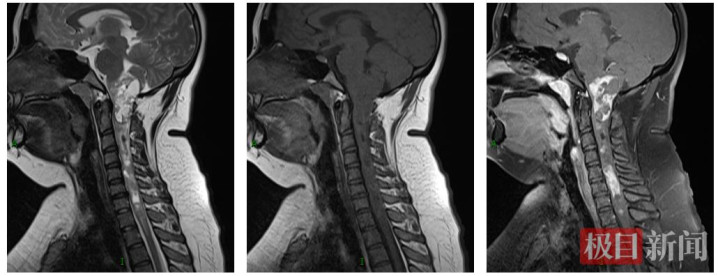

术前MRI显示,病灶从延髓向下串联、延伸至胸1椎体水平